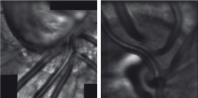

- eFig. 9-11 - Élongation des pores en inférieur correspondant à un déficit supérieur du champ visuel

- eFig. 9-12 - Élongation des pores en supérieur correspondant à un déficit supérieur des fibres nerveuses rétiniennes à l'OCT